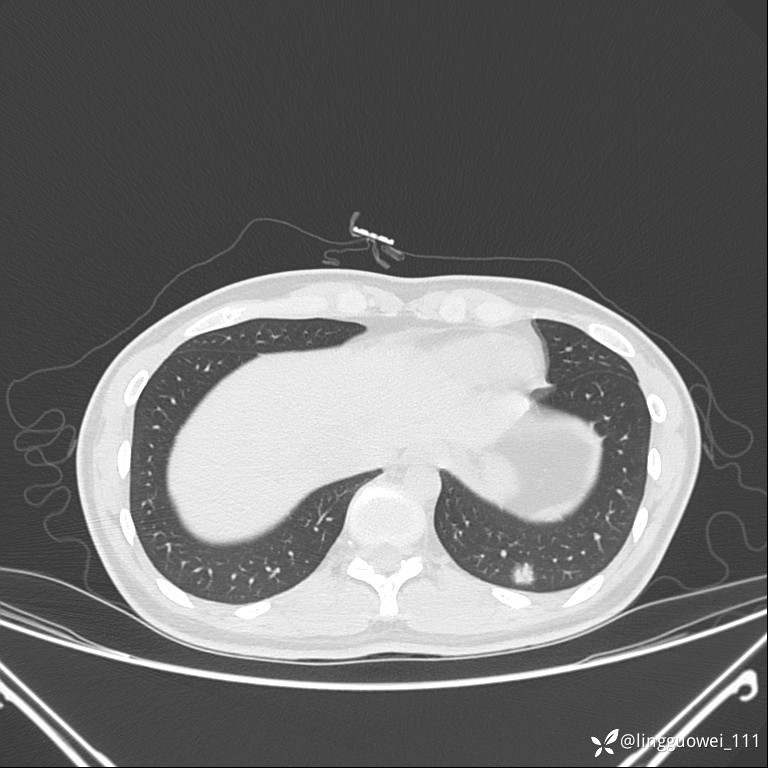

年轻女性咳嗽,CT发现肺结节,良性还是恶性?(4天后公布结果)

患者性别:女

患者年龄:26岁

主诉:咳嗽来诊,结节性质不明。

肺毛细血管瘤 (2)